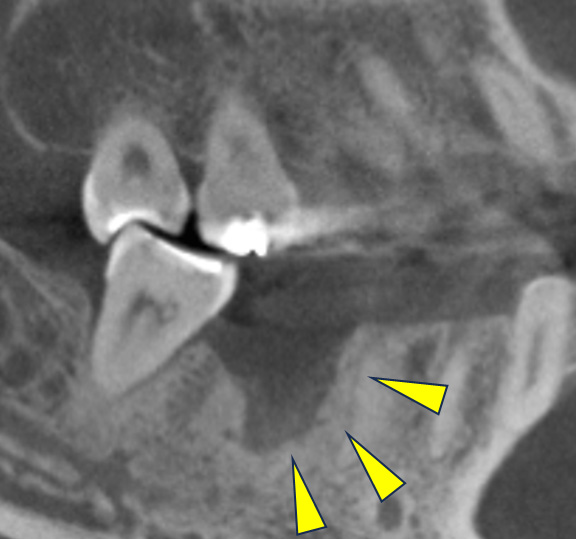

CT画像 -

骨移植(人工骨+メッシュプレート)を行い、骨を造りました。